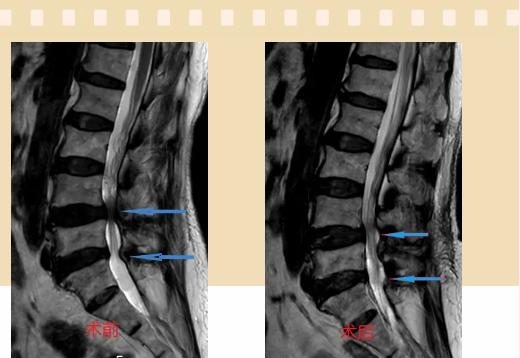

入院后李鵬副主任醫(yī)師為其進行了詳細的查體,完善了術(shù)前的檢查,明確診斷為:腰椎管狹窄癥(L4/5、L5/S1),病人合并2型糖尿病,請內(nèi)分泌科會診,穩(wěn)定血糖后,麻醉科會診病人,排除手術(shù)禁忌,李鵬為病人制定了手術(shù)方案:單側(cè)入路雙側(cè)減壓(ULBD)。

手術(shù)采用三個微創(chuàng)小切口,兩個節(jié)段減壓手術(shù)時間2.5小時,出血50ml。術(shù)后2天腰圍保護下床活動,術(shù)后5天順利出院。

傳統(tǒng)腰椎管狹窄癥的手術(shù)治療,往往需要切開減壓,同時需要內(nèi)固定融合術(shù),創(chuàng)傷很大,同時可能需要輸血,臥床時間較長,病人合并糖尿病,感染風險也高,而本次采用的UBE-ULBD手術(shù)切口更?。悠饋砑s3cm,如果是單節(jié)段狹窄只需要不到2cm切口)、創(chuàng)傷更小,術(shù)后恢復較快,可以更早地恢復正?;顒?。

此外,手術(shù)保留了病變節(jié)段的穩(wěn)定性,是一種微創(chuàng)的椎管減壓手術(shù),能通過切除部分椎板、關節(jié)突關節(jié)、黃韌帶來解除神經(jīng)根和硬膜囊的壓迫,不需要額外行腰椎內(nèi)固定術(shù),不需要螺釘及融合器的植入,病人術(shù)后腰椎的活動度不受影響。(盧   闖  劉   旭   袁錦鈺)